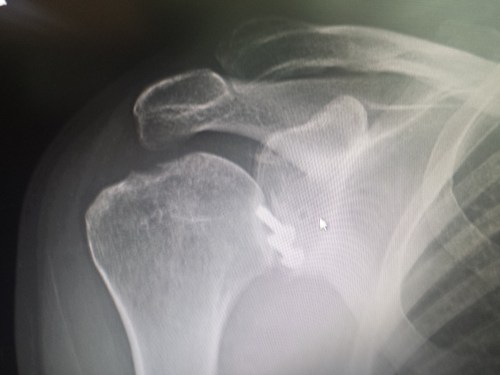

It has been almost three months since my last post here, and things have fallen quiet on our sister blog Anatomy to You, too. I thought it was time for an update, which is mostly a summary of stuff we’ve been doing on my team, but also featuring some interesting images if you stick around. The relative silence here has partly been due to me giving myself some nice holiday time w/family in L.A., then having surgery to fix my right shoulder, then recovering from that and some complications (still underway, but the fact that I am doing this post is itself evidence of recovery).

X-ray of my right shoulder from frontal view, unlabelled

Labelled x-ray